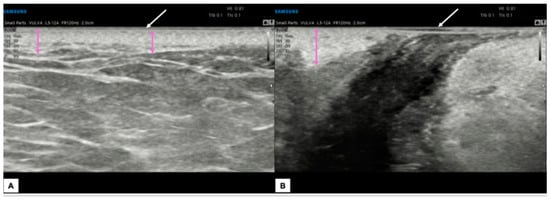

- The vulva should be virtually visualized as a clock face and divided into four quadrants according to the ISSVD nomenclature [14] by an imaginary vertical line that passes through the clitoris and the anus (defining the lateral sides—right and left) and a horizontal line from the upper border of the hymenal ring (defining the anterior and posterior portions) (Figure 3A). This allows the vulva to be studied in its entirety and to describe the location and extension of vulvar lesions accurately.

- The probe should be placed in a transverse position at the beginning of the examination, and the clitoral area should be assessed first. From here, the examination should continue clockwise to study the remaining areas (Figure 3B).

- Once the clockwise rotation is completed and the clitoral area is reached again, the probe should be placed longitudinally and, starting at the level of the vestibule, moved laterally, first one way and then the other, extending it to the outer edge of the labia majora (Figure 3C). During this phase, an additional amount of gel should be applied to increase the distance between labia minora and majora to distinguish the different layers better [4]. A linear probe, preferably > 15 mHz (HFUS), is recommended to achieve optimal skin layer stratification [15]. The physiological presence of pubic hairs can alter the sonographic image. For this reason, some authors indicated hair removal the day before the imaging is performed.